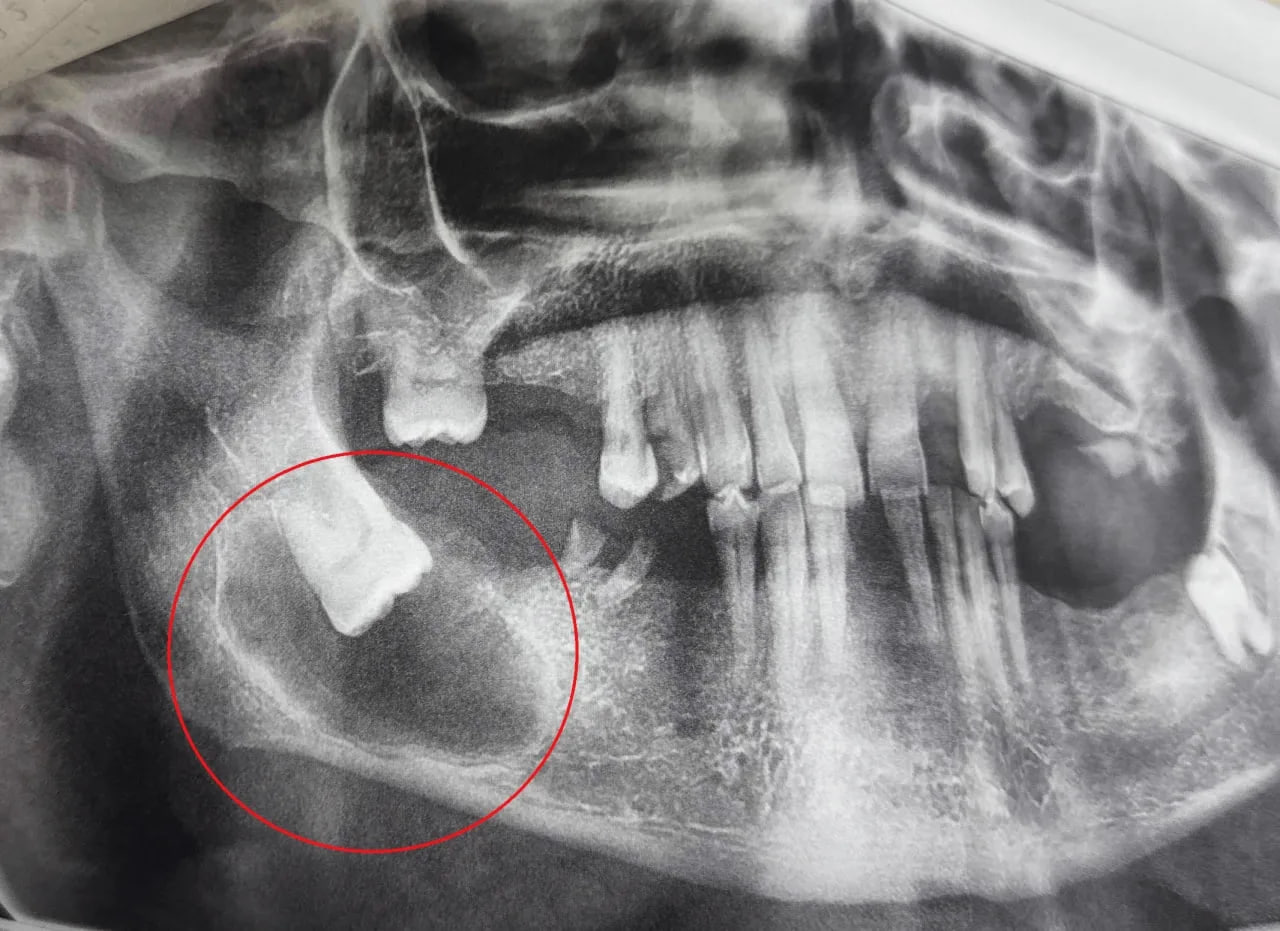

В областную стоматологическую поликлинику обратился 65-летний мужчина с жалобами на ноющие боли в нижней челюсти справа, чувство распирания и асимметрию лица. Врачи обнаружили ретинированный зуб мудрости, расположенный горизонтально, и фолликулярную кисту вокруг него.